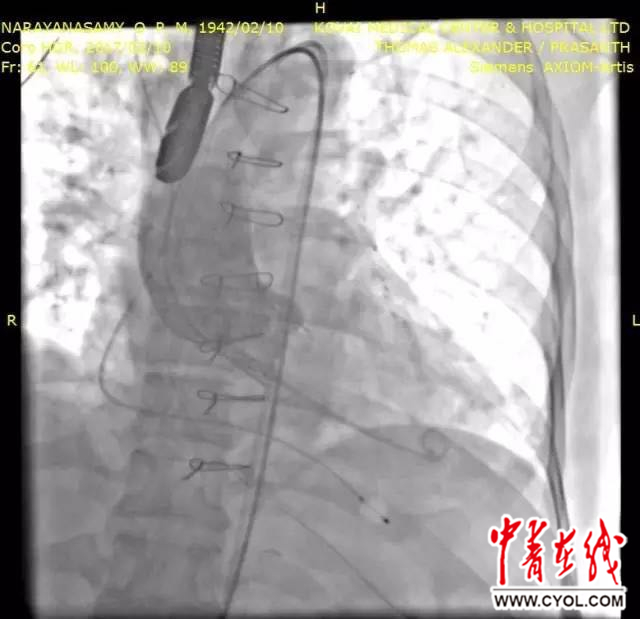

中青在线杭州2月11日电(中国青年报·中青在线记者 李剑平)今天,据浙江大学医学院附属第二医院介绍,该院院长王建安2017年2月10日受邀到印度哥印拜陀的科瓦伊医学中心(Kovai Medical Center and Hospital, KMCH),成功为一名重症患者开展经导管主动脉瓣置换术(Transcather Aortic Valve Replacement, TAVR)。王建安教授还向印度医院的医护人员进行了详细的演示及手术带教。

此次采取手术治疗的患者为一位75岁的老年男性,反复出现严重的胸闷气急,诊断为主动脉瓣重度狭窄,并有高血压、糖尿病、冠心病病史,在

2012年接受了心脏外科搭桥手术。

对于该患者,再次进行传统的外科开胸手术风险极高,若不及时治疗,患者随时有生命危险。

KMCH邀请王建安教授采用最新的经导管介入治疗方法救治该患者。针对患者二叶式主动脉瓣畸形,而且钙化不对称,解剖学结构难度高,王建安教授针对性地采用自己团队研发的新技术,成功为该患者进行了经导管介入换瓣治疗,其中新一代瓣膜为中国制造。